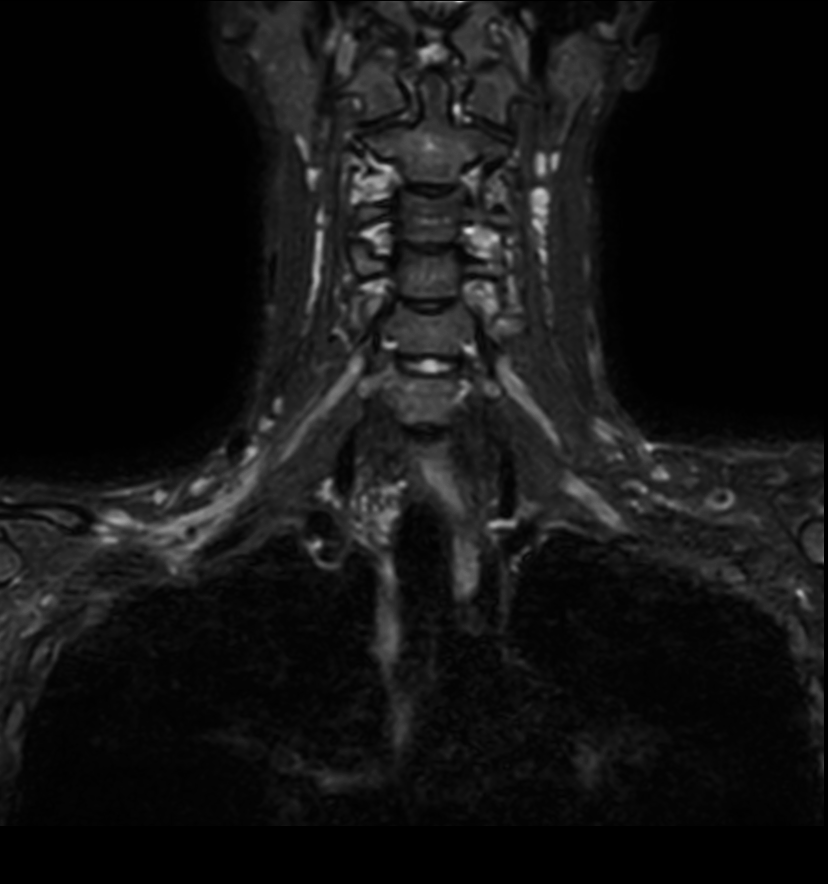

Coronal 3D STIR